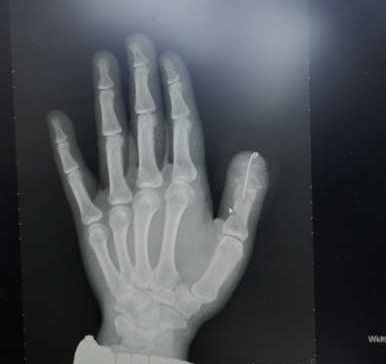

患者张某,在用千斤顶换轮胎时,千斤顶突然坠落,砸中左手拇指,因剧烈疼痛,本能抽手导致拇指末节完全撕脱离断,当场鲜血直流,自行包扎后,送至市人民医院显微外科就诊。显微外科立即开通绿色通道,给予包扎止血,并拍片、做心电图等做好术前准备。因断指需在6小时内血管通血才能保证再植的成功,患者拇指系撕脱离断伤,血管神经撕脱,血管条件较差给再植增加了很大难度,且不能保证100%成活。如给予行拇指游离移植第二足趾再造术,其创伤较大,缺失一足趾,外观差,经会诊后,全科一致认为拇指占手部功能的50%,再植难度再大也要克服,与患者家属沟通后,患者全力配合手术。

术前准备有条不紊的进行,手术室已做好各项准备工作,患者一入手术室即刻进入手术状态,显微镜下清创探查见拇指双侧指动脉撕脱,挫伤明显,指动脉管径较细,标记后,拇指以克氏针固定,显微镜下再次清创,因拇指指动脉末节血管管径较细,以12/0无损伤缝合线吻合,吻合血管时为避免因大的动作再次损伤血管,需手术医生平心静气容不得半点闪失,血管接通后见通血良好,拇指颜色红润,经过4个小时紧张的手术,终于将离断的拇指再植成功,血管通血良好预示着再植成功,大家悬着的心终于落地了。术后给予“三抗”治疗,术后七天成功度过危险期,再植拇指成活,现患者已出院,拇指外形良好。